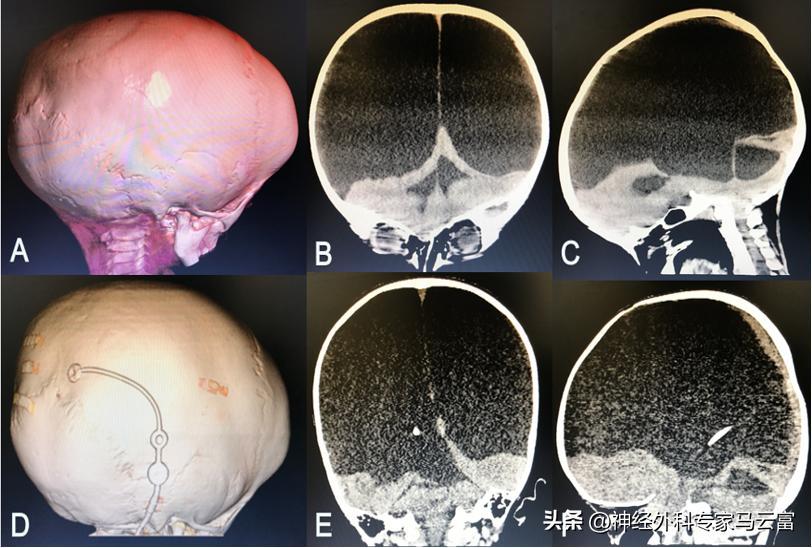

最近省婦幼神經外科收到一個頭大的腦積水寶寶,患兒頭異常大。

患兒頭大的寶寶

患兒顱腦CT